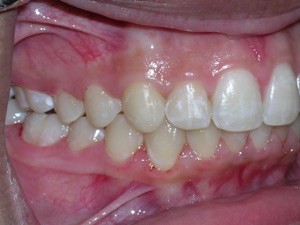

In this case, a young woman came to us with a desire to straighten her teeth. We elected to do Invisalign treatment with some enamel reduction and some dental arch expansion. Take a look...

Here she is on the day of appliance removal. You can see how the crossbite on the right has improved, as well as the lower front teeth crowding. Note that we elected to leave the lower second premolar in it’s rotated form.